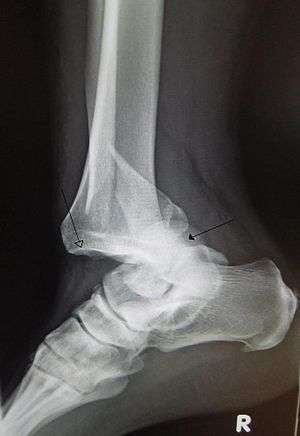

| A traumatic dislocation of the tibiotarsal joint of the ankle with distal fibular fracture. Open arrow marks the tibia and the closed arrow marks the talus. | |

X-rays are usually taken to confirm a diagnosis and detect any fractures which may also have occurred at the time of dislocation. A dislocation is easily seen on an X-ray.[8]

It is important the joint is reduced as soon as possible, as in the state of dislocation, the blood supply to the joint (or distal anatomy) may be compromised. This is especially true in the case of a dislocated ankle, due to the anatomy of the blood supply to the foot.[10]